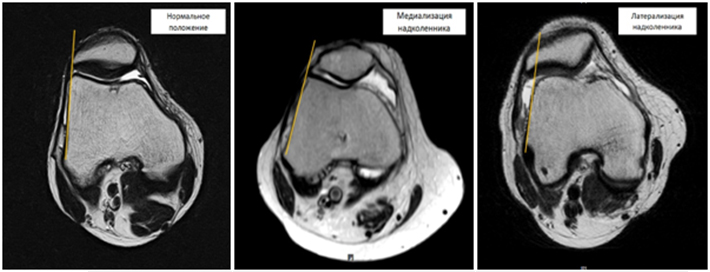

Лечение медиализации (смещение внутрь) и латерализации (смещение наружу) надколенника

Медиализация (смещение внутрь) и латерализация (смещение наружу) надколенника – наиболее часто встречающееся осложнение дисфункции капсульно-связочного аппарата коленного сустава. Данное заболевание сопровождается незначительными болями и «хрустом» в области коленного сустава, которые возникают при сгибании коленного сустава и при длительном сидении с согнутыми в коленях ногами. Незначительные, вначале, боли со временем усиливаются, приобретают ноющий характер и стремление пациентов сидеть с вытянутыми (разогнутыми в коленях) ногами. Данное заболевание приводит к развитию артроза надколенниково-бедренного (пателло-феморального) сустава и значительному снижению качества жизни.

Дислокация (медиализация или латерализация) надколенника могут быть как врожденными, так и приобретенными. Врожденная дислокации надколенника обусловлена неправильным развитием собственной связки надколенника и неправильным формированием точки прикрепления этой связки, что приводит к нарушению оси скольжения надколенника по бедренной кости и его смещению. Приобретенная дислокация надколенника развивается в результате травм области коленного сустава, которые приводят к полному или частичному повреждению наружной или внутренней натягивающей связки надколенника. Обычно повреждения натягивающих связок надколенника не диагностируются, а боли проходят через 5-7 дней после травмы. Поврежденная связка срастается с формированием рубца, который со временем растягивается в результате чего нарушается равнодействие боковых сил, действующих на надколенник, и последний смещается или наружу, или во внутрь.